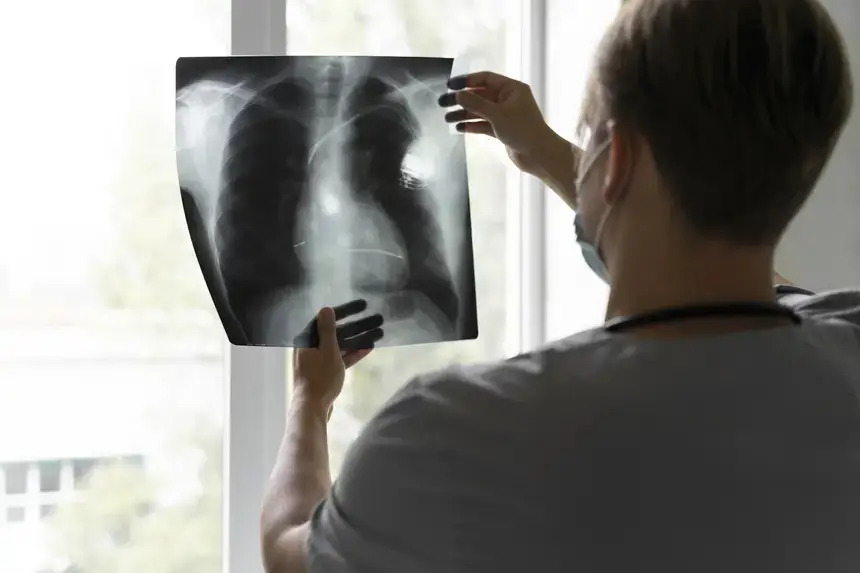

A tuberculose é uma doença infecciosa causada por uma bactéria que atinge principalmente os pulmões e é transmitida pelo ar. Os principais sintomas são tosse persistente, perda de peso, febre e cansaço. Ao apresentar esses sinais, a orientação é procurar uma Unidade Básica de Saúde (UBS), porta de entrada para o diagnóstico e encaminhamento.

Entre os exames ofertados pelo CRDT estão o teste rápido molecular, que detecta a doença em poucas horas, e a baciloscopia (BAAR), que identifica a presença do bacilo no escarro. A realização desses exames é essencial para o controle da doença e a redução da transmissão.